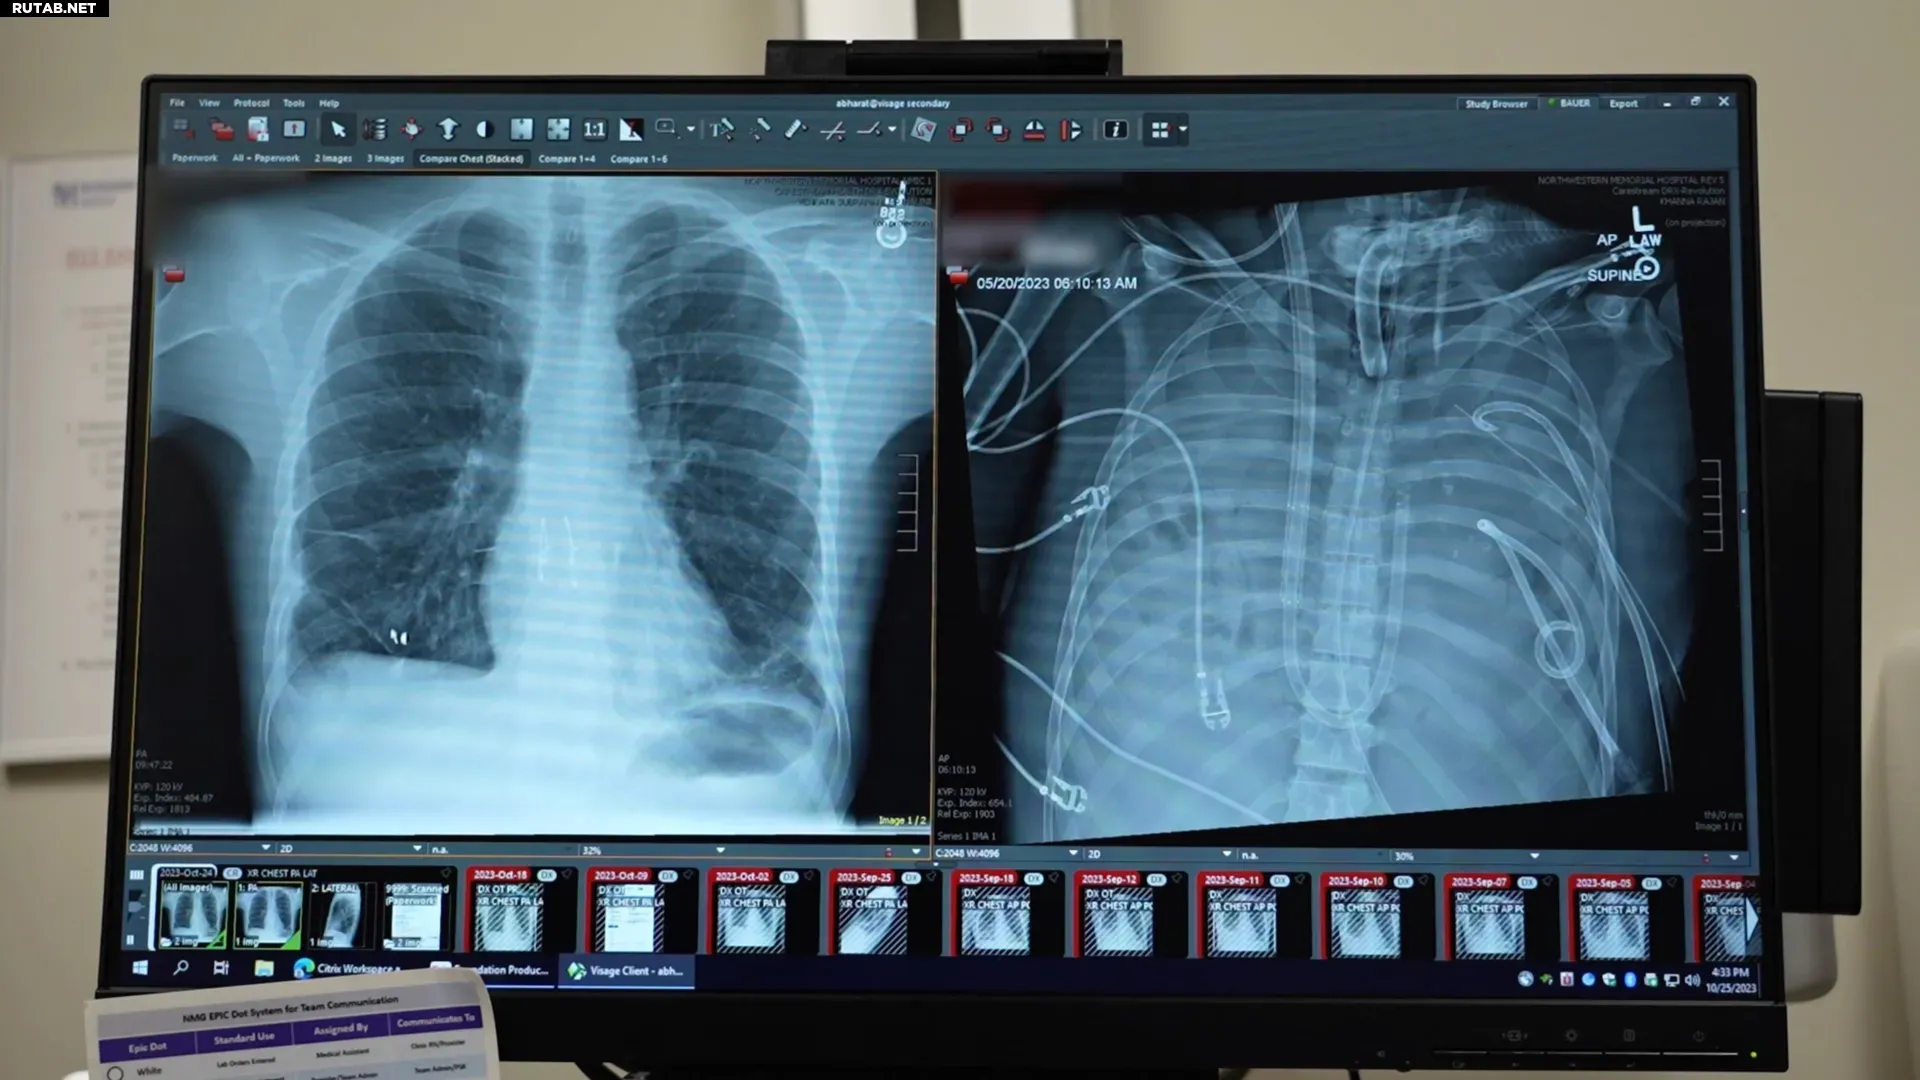

Новые (слева) и удалённые (справа) лёгкие пациента. Фото: Northwestern Medicine

Человек не может жить без лёгких, но один пациент сумел прожить без них 48 часов. В журнале Med хирурги описали случай, когда они удалили мужчине тяжело инфицированные лёгкие и использовали систему «искусственного лёгкого», чтобы поддерживать его жизнь до проведения трансплантации. Этот случай демонстрирует потенциально новый способ спасения критически больных пациентов в ожидании донорских органов.

33-летний пациент страдал от острого респираторного дистресс-синдрома (ОРДС), начавшегося с гриппа и осложнившегося бактериальной пневмонией. Его лёгкие, сердце и почки стали отказывать. Лёгкие были настолько повреждены, что их удаление стало необходимым, но тело пациента было слишком нестабильным для немедленной пересадки.

Медицинская команда разработала искусственную лёгочную систему, которая временно взяла на себя функции лёгких: насыщала кровь кислородом, удаляла углекислый газ и поддерживала кровообращение. После удаления повреждённых лёгких состояние пациента стабилизировалось, органы начали восстанавливаться, а инфекция — контролироваться. Через два дня появились донорские лёгкие, и операция по их пересадке прошла успешно. Спустя более двух лет пациент ведёт нормальную жизнь со здоровой функцией лёгких.